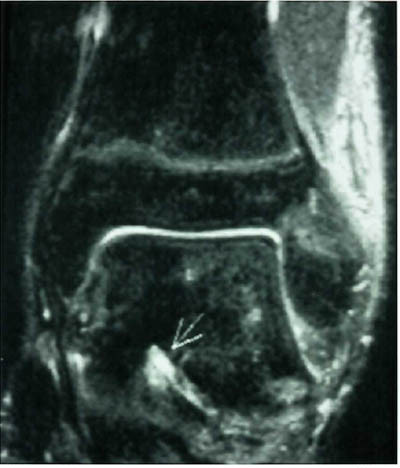

Mesteparten av sinus tarsi er fylt med fett. Dette gir høysignal på T1-vektet sekvensog lavsignal på fettsuppresjonssekvenser. Blodkar og nervefibrer gir små punktformige lavsignaler medialt i fettvevet på T1-vektet sekvens. Ligamentene gir lavsignal på spinnekkosekvensene. Figur 1 viser en normal sinus tarsi. I koronalplanet sees ligamentum cervicale ventralt og ligamentum interosseus noe lenger dorsalt. Det mest fremtredende og hyppigste MR-funnet ved sinus tarsi-syndrom er lavsignalområder på T1-vektet sekvens og lav- eller høysignalområder på T2-vektet sekvens. Forandringene er forårsaket av fibrose (fig 2) med eller uten inflammasjon (fig 3). Av og til kan vi se små væskelokulamenter som representerer ganglioncyster (fig 4). Ligamentene kan være vanskelig å se, enten fordi det er mye inflammasjon eller fordi de er røket. Hos en del pasienter kan man finne ruptur av laterale ankelligamenter, spesielt ligamentum talofibulare anterior.

Sinus tarsi-syndrom er i de fleste tilfeller en klinisk diagnose. Men av og til kan det være vanskelig å stille diagnosen klinisk. MR vil være til stor hjelp. Fibrose og/eller inflammasjoner gir karakteristiske MR-funn. Ligamentrupturer diagnostiseres ved manglende fremstilling, gjennomgående høysignal eller abnormt forløp. Ganglion utgående fra sinus tarsi kan også gi symptomer (10).

I tillegg til å kunne påvise patologiske forandringer i sinus tarsi kan vi påvise andre årsaker til smerter lateralt i bakfoten: Osteokondrale skader ved øvre laterale talushjørne, avaskulære nekroser og stressfrakturer i omliggende knokler samt patologi i omliggende ligamenter og sener (fig 5) og (fig 6).